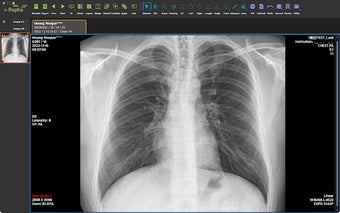

IRM iExtension - это дополнение для Chrome, которое предоставляет поддержку нескольких мониторов и функциональность загрузки файлов DICOM для просмотра изображений DICOM в продукте WebPACS от IRM. С установленным этим расширением медицинские специалисты могут максимально использовать функцию нескольких мониторов и отображать радиографические изображения пациентов на нескольких экранах в соответствии с протоколом DICOM Hanging.

С фокусом на улучшении опыта использования нескольких мониторов и обеспечении простой загрузки файлов DICOM, IRM iExtension является ценным инструментом для медицинских специалистов, использующих DICOM Image Viewer в IRM WebPACS. Его безшовная интеграция с Chrome делает его легко доступным и удобным в использовании.